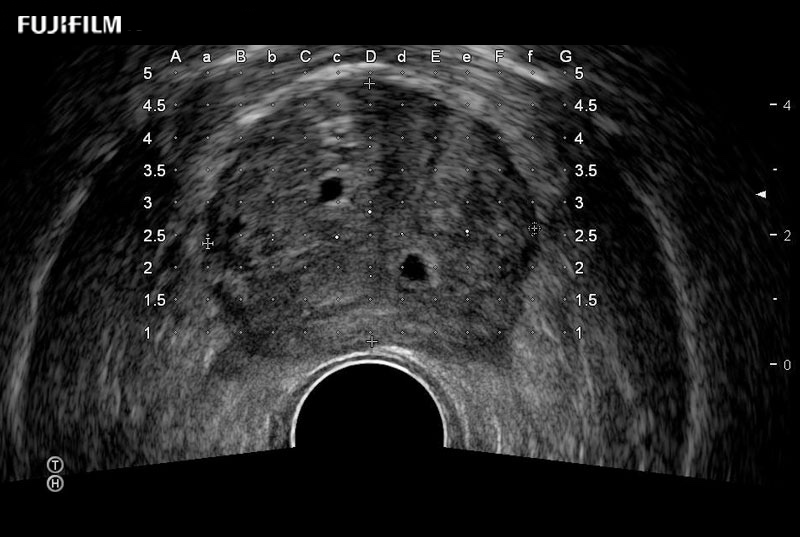

Exclusive 200° FOV end-fire prostate biopsy transducer.

Provides real-time imaging of both the sagittal and transverse planes